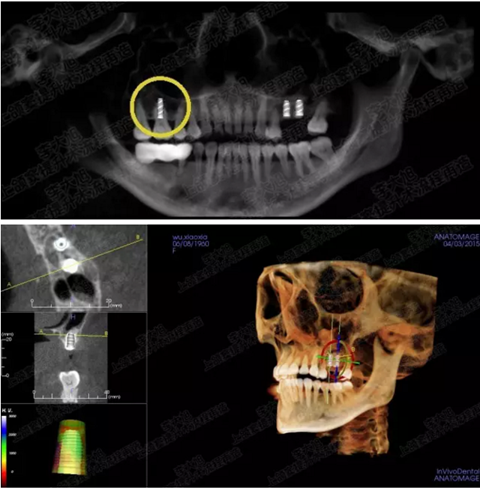

病例一

上頜竇多分隔3mm

05.png

提升8mm

06.png

07.png

修復(fù)時根尖片

08.png

09.png

口內(nèi)照片

001.png

修復(fù)后一年

002.png